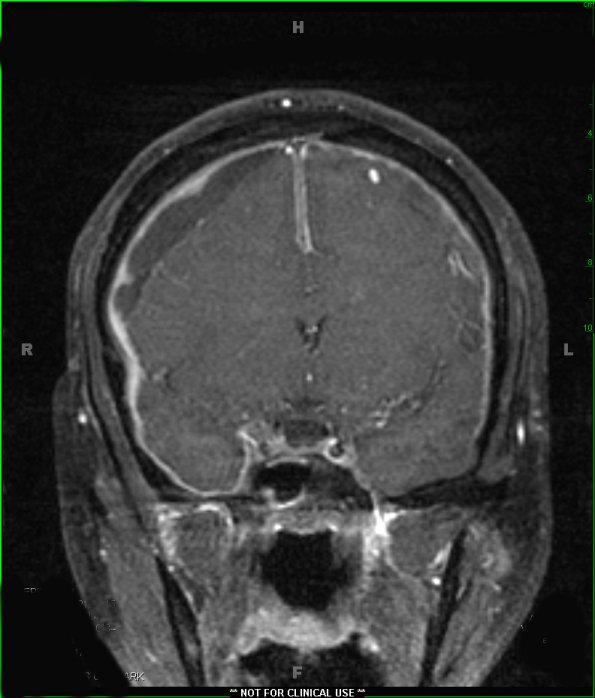

T1-weighted coronal image with contrast shows bilateral extraparenchymal lesions which enhance with contrast (1A2).